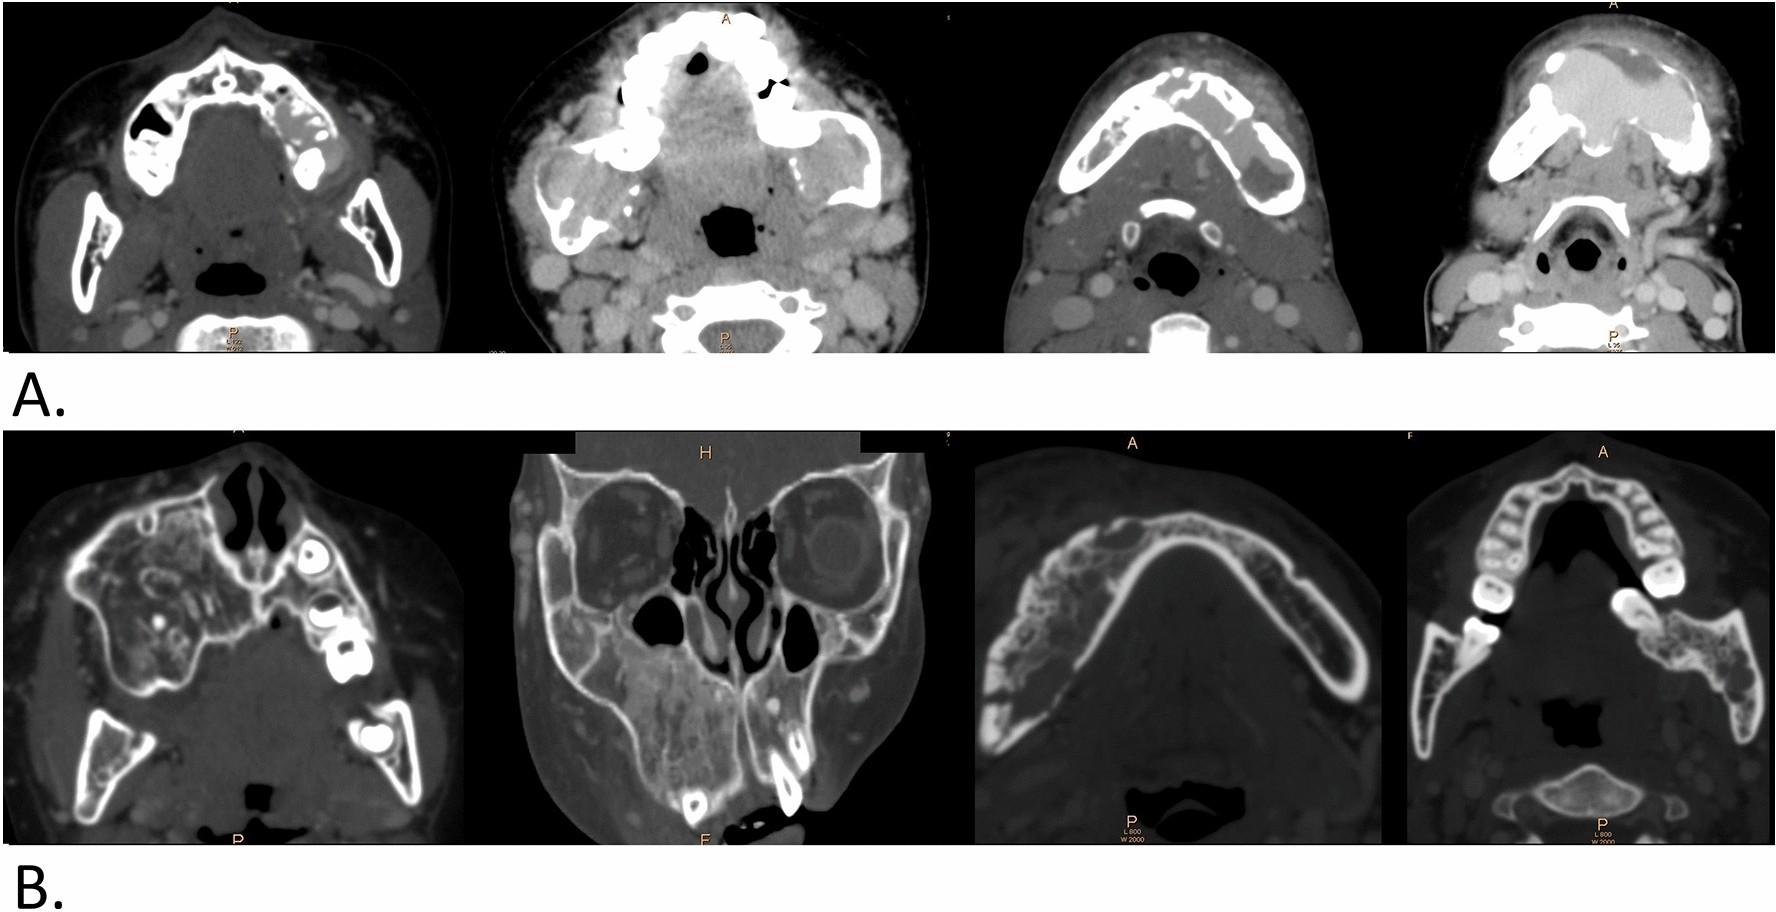

Figure 3

Enhancement in the cancellous bone on contrast-enhanced CT and manifestations of j-AVMs. Enhancement (a) centred on the root of the left first molar in the maxilla; the cancellous bone of the bilateral mandibular ramus; the anterior and posterior region of the mandible on the left side; the anterior region of the mandible with destruction and penetration of the cortical bone. (b) Irregular hyperosteogeny, with disordered and heterogeneous bone density and structure on contrast-enhanced CT and manifestations of j-AVMs. Irregular hyperosteogeny involves the whole maxilla of the left side; buccal cortex of the right mandible; area around the root of the teeth.